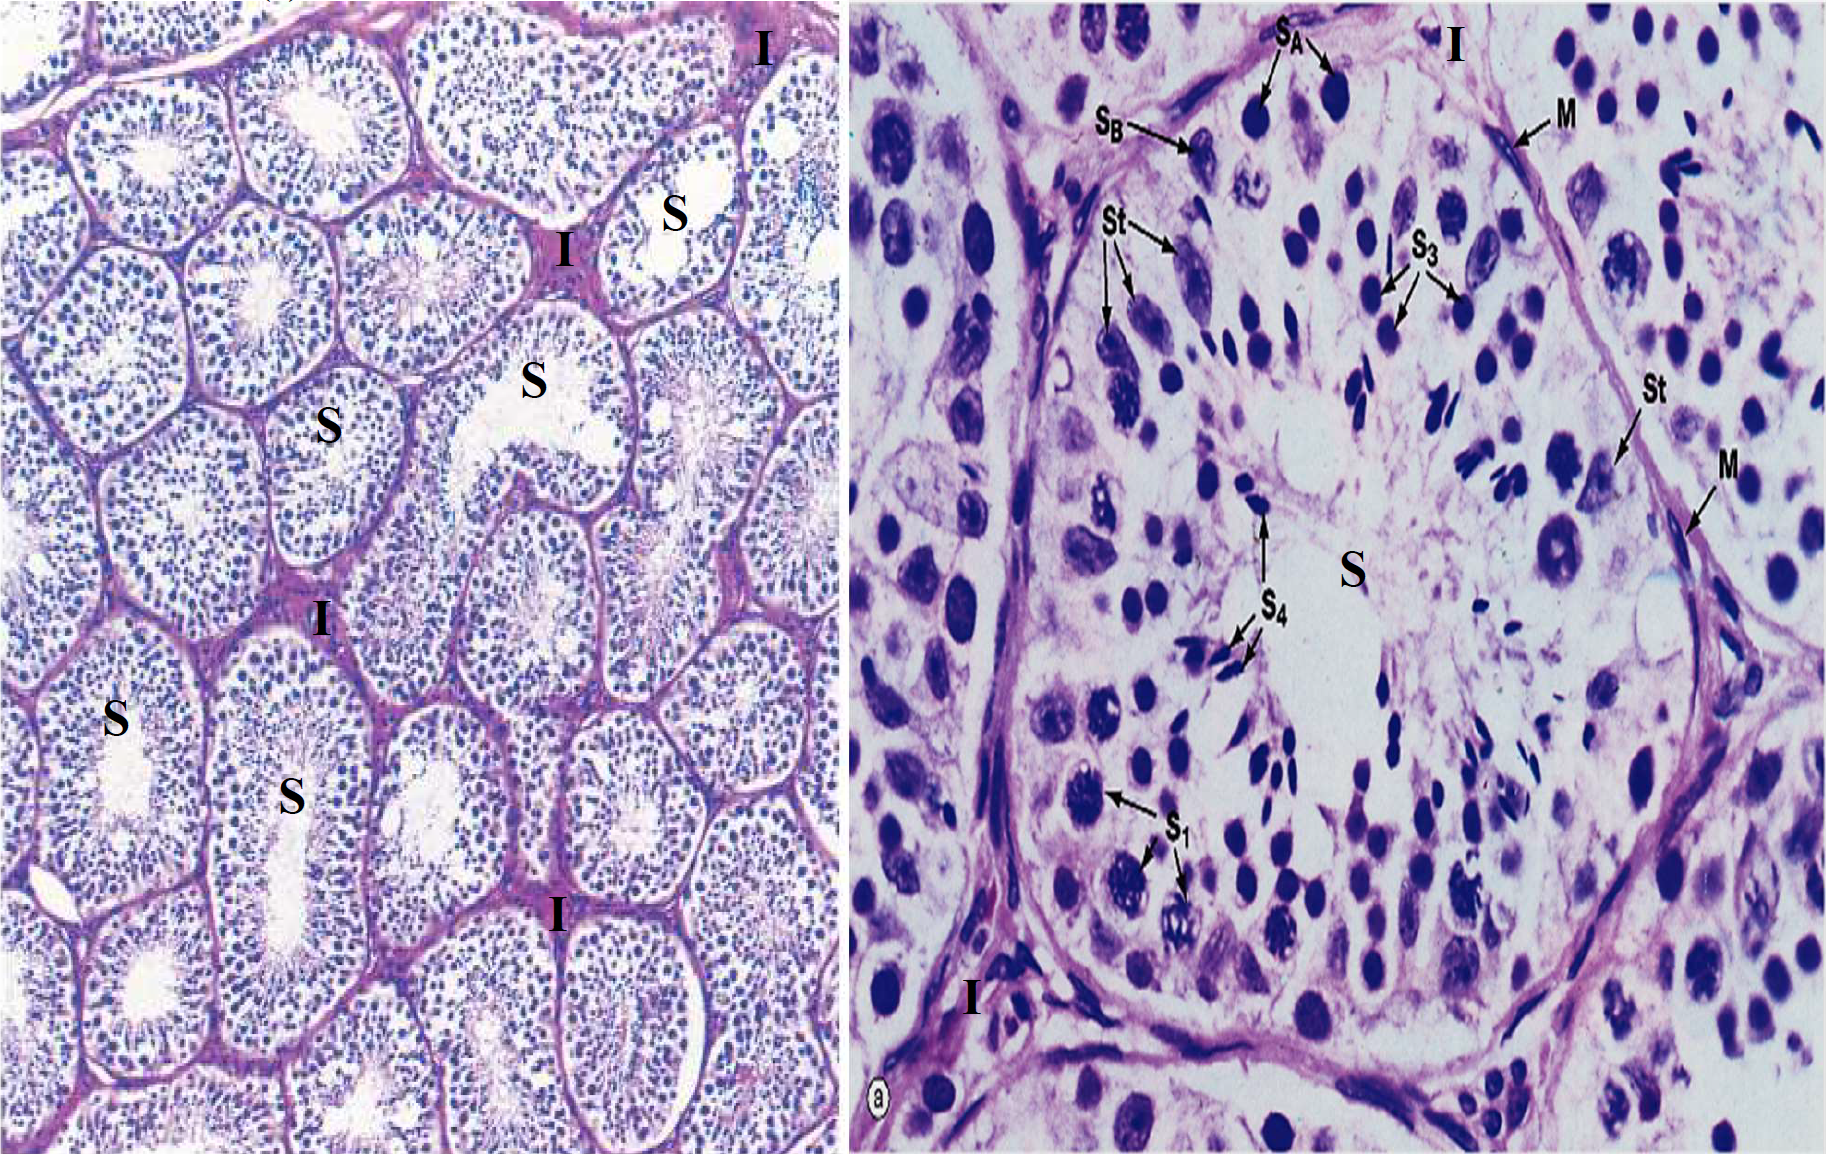

- 約250 個小葉

- TA: Dense irregular

- Tunica (lamina) propria

- Wave of the seminiferous tubule

- 支持細胞

- 長核,淡染

- 核仁明顯(Karyosome)

- 血睪障壁(blood-testis barrier),阻擋免疫

細胞質會一直黏在一起

- Spermatogonia (SA, SB)

- Primary spermatocyte (S1)

- Spermatid (S3)

- Spermatozoa (S4)